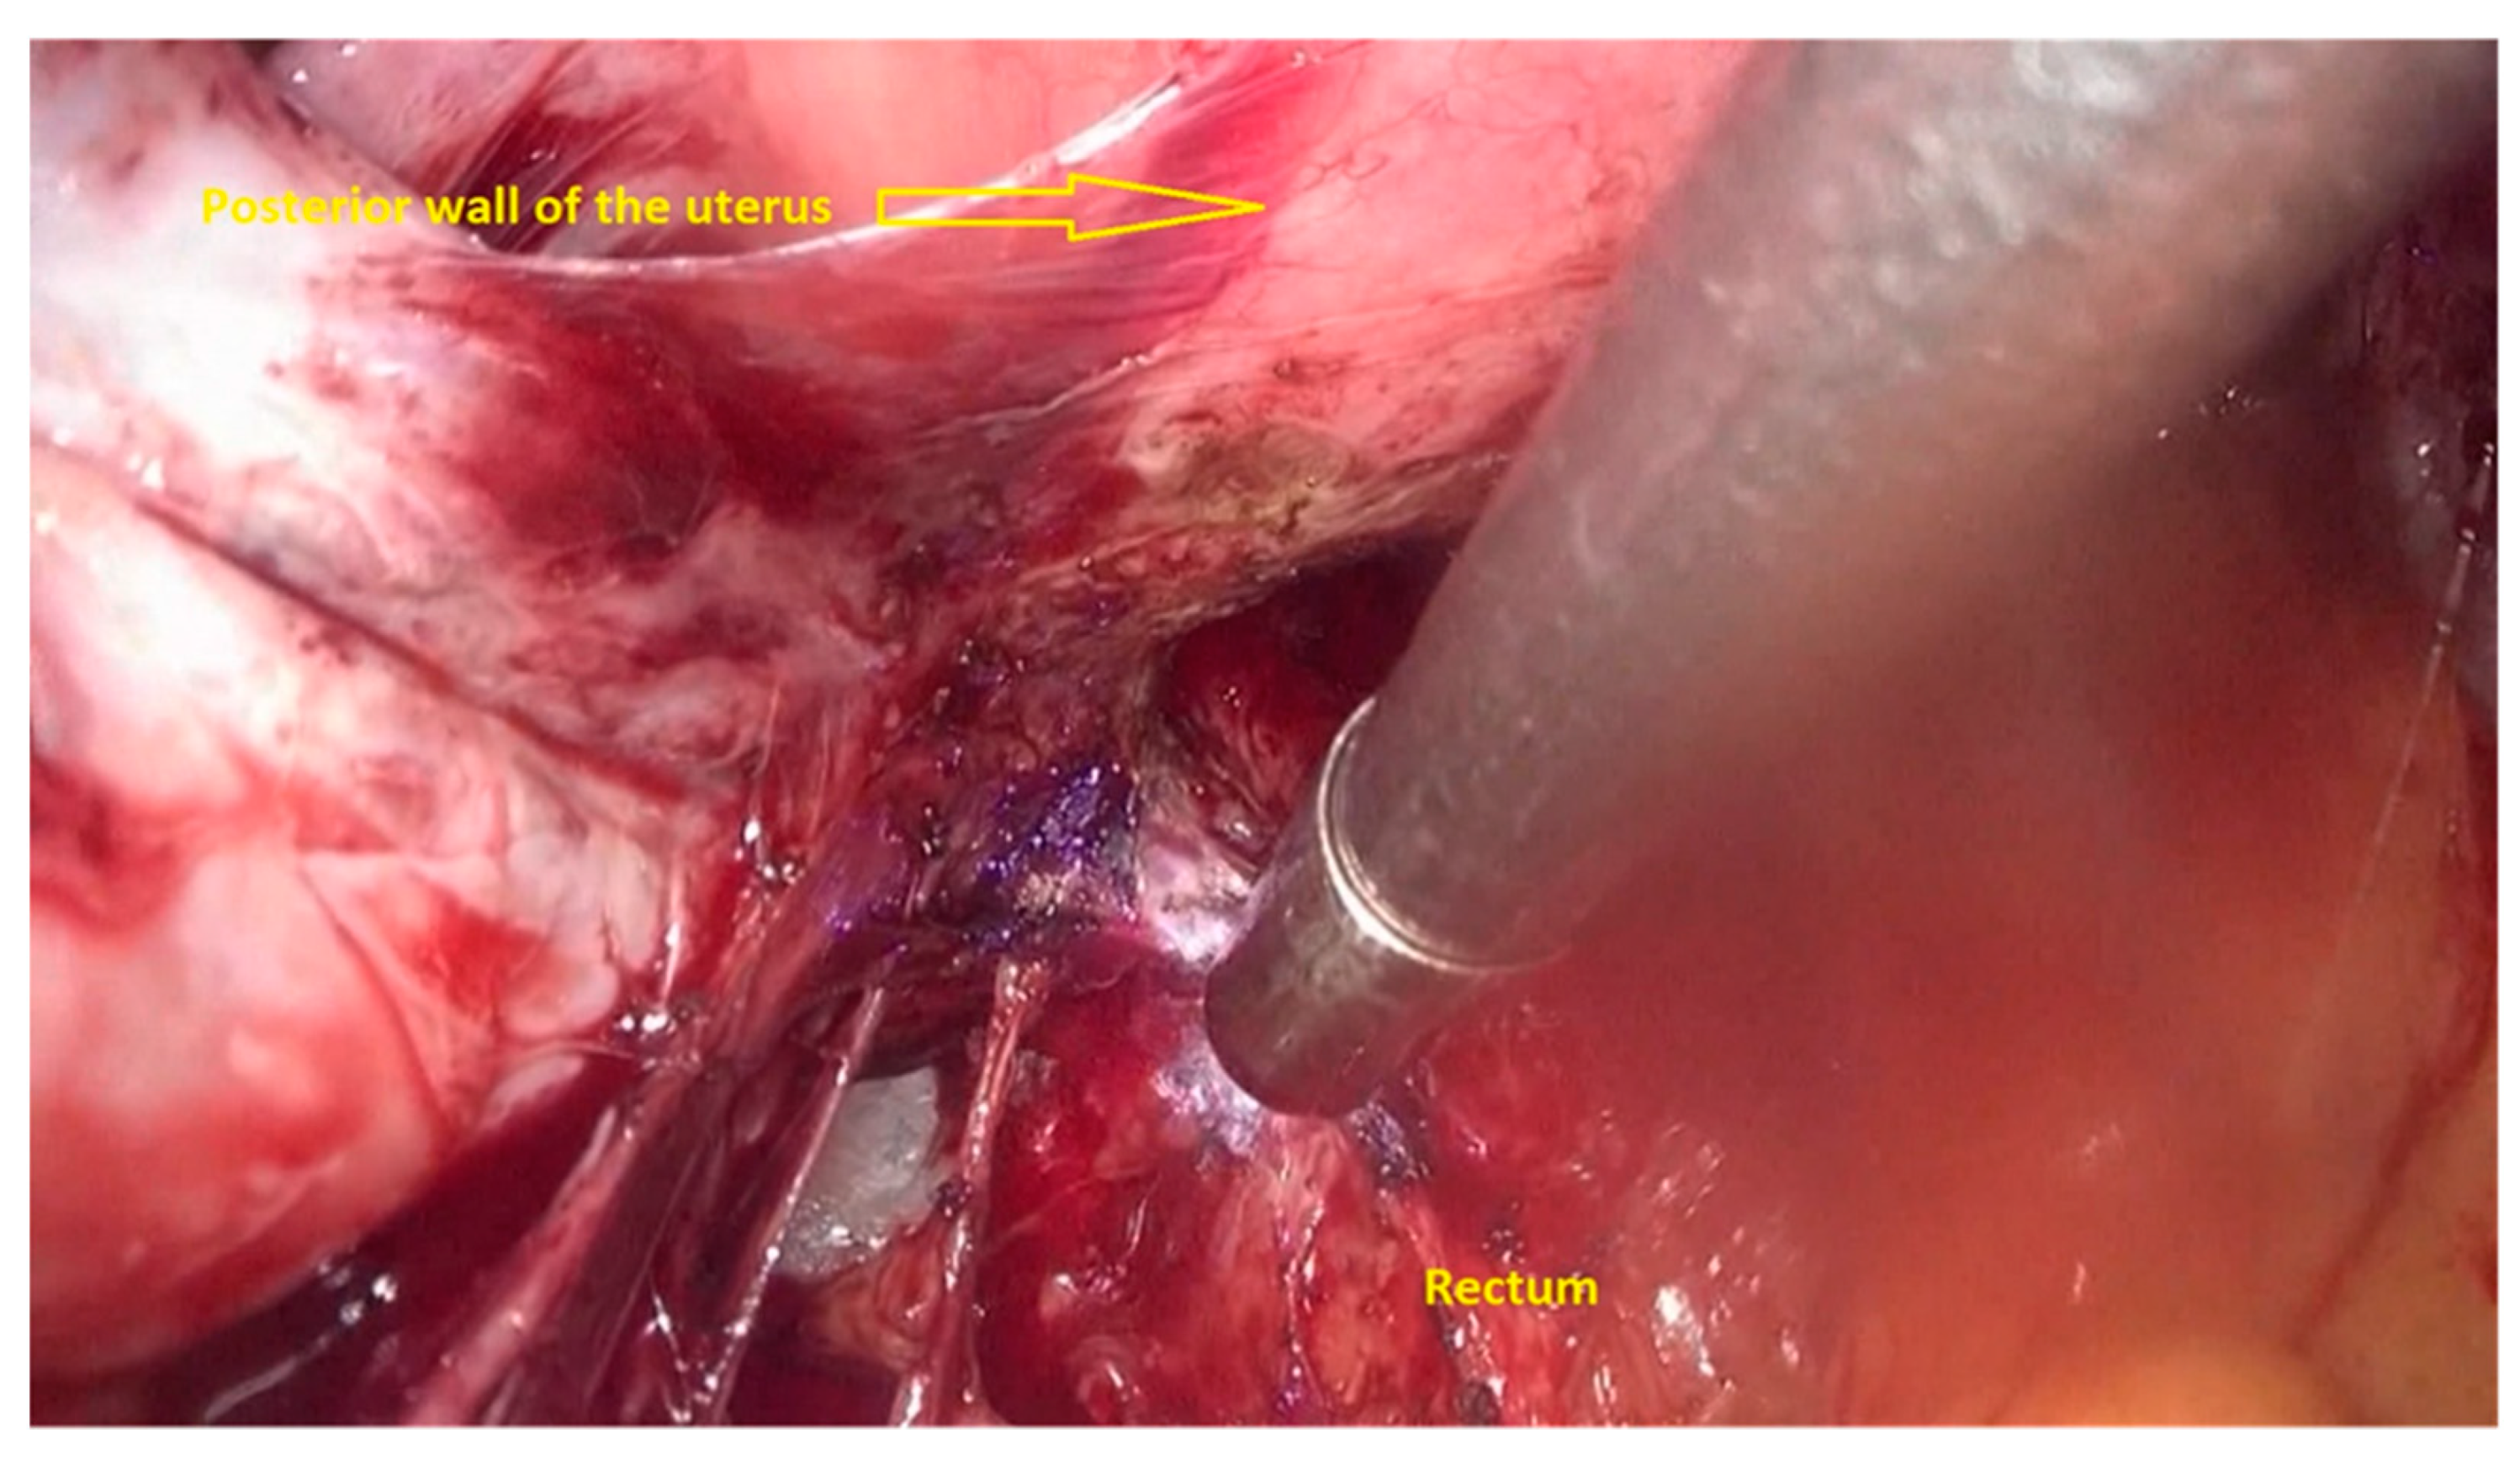

- The deep rectal spaces and rectovaginal septum surrounding the rectal nodule are opened in an anterolateral plan while staying connected to the levator ani muscle and with the preservation of fascia recti (Figure 3).